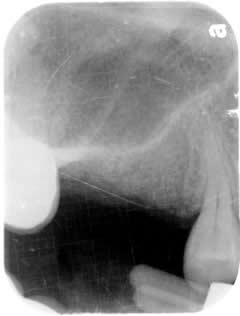

Sinus Lift:

The white line you see if the floor of the maxillary sinus. Above the white line is the sinus, air-filled sac. There is no bone in the sinus.

Extra bone graft is needed to lift the floor of the sinus. This procedure is called Sinus Lift.